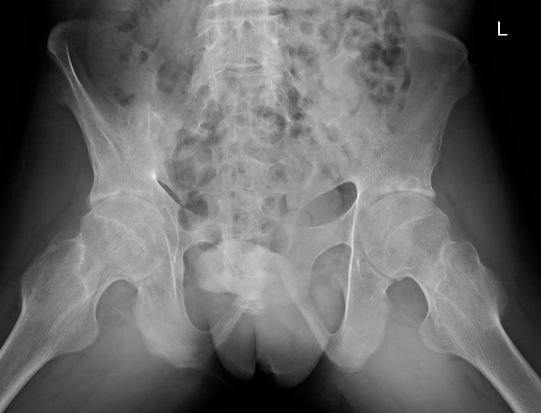

例2:29岁男性,AS患者,双髋、双膝关节疼痛伴活动受限6年